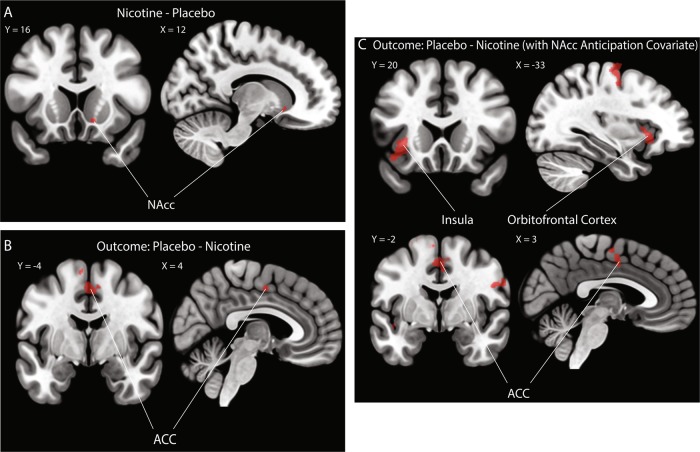

First, we were interested in replicating our prior work in an independent sample [25] where participants showed significantly greater NAcc activity to reward anticipation when they were administered nicotine compared to placebo. We conducted a two-sample paired t-test with a small-volume correction using an anatomical bilateral NAcc mask [41]. Replicating prior findings, participants showed significantly stronger NAcc activation during the nicotine compared to placebo visit (Fig. 1; peak z-stat = 3.78 at MNIx,y,z = 12, 18, −6, pcorr = 0.031). Also in line with prior reports, no activation was significant when comparing nicotine and placebo during reward outcome.

Fig. 1. Effect of nicotine on corticostriatal activity to reward processing.

a NAcc activity between nicotine and placebo visits. Acute nicotine administration significantly increased participants’ NAcc activity during reward anticipation. All voxels passed an initial cluster-forming threshold of z = 3.1, with small-volume correction within the anatomical NAcc using a cluster-extent threshold of p < 0.05. b PPI analysis of functional connectivity between NAcc and other brain regions. Acute nicotine administration significantly decreased the functional connectivity between NAcc and the ACC/MCC during reward outcome but not anticipation. c After adding in participants’ NAcc activation during reward anticipation as a covariate, the PPI model revealed that acute nicotine administration significantly decreased the functional connectivity between NAcc and three cortical regions (i.e., ACC, OFC and insula) during the reward outcome phase. All areas of activation passed an initial cluster-forming threshold of z = 2.3, with whole-brain cluster-extent threshold at p < 0.05.

In our PPI model, we used an anatomical bilateral NAcc as our seed region to identify regions whose connectivity with the NAcc increases during reward anticipation or outcome phases. We directly compared connectivity changes under placebo relative to nicotine administration using a two-sample paired t-test. For the placebo—nicotine contrast, we found a cluster within the anterior cingulate cortex (ACC) extending into the anterior midcingulate cortex (aMCC; Fig. 1b; peak z-stat = 3.15 at MNIx,y,z = 4, −4, 50 pcorr = 0.0029) exhibited significantly greater connectivity with the NAcc during the outcome phase under placebo relative to nicotine (contrast of placebo—nicotine). No differences in functional connectivity were noted when assessing nicotine administration vs. placebo (contrast of nicotine—placebo). No contrasts for the anticipation phase survived correction.

To further examine the effect of nicotine on corticostriatal functional connectivity during the outcome phase, we included each participant’s NAcc PE during anticipation as a covariate into the PPI model. The inclusion of the covariate into the PPI model allowed us to test for regions whose connectivity with NAcc increases during the outcome phase as a function of their NAcc activity during the anticipation phase. For the contrast of placebo—nicotine, after accounting for NAcc anticipation as a covariate, we found a significant cluster in the orbitofrontal cortex (OFC), insula, and ACC (Fig. 1c; peak z-stat = 3.75 at MNIx,y,z = −32, 20, −2, pcorr = 0.0098).